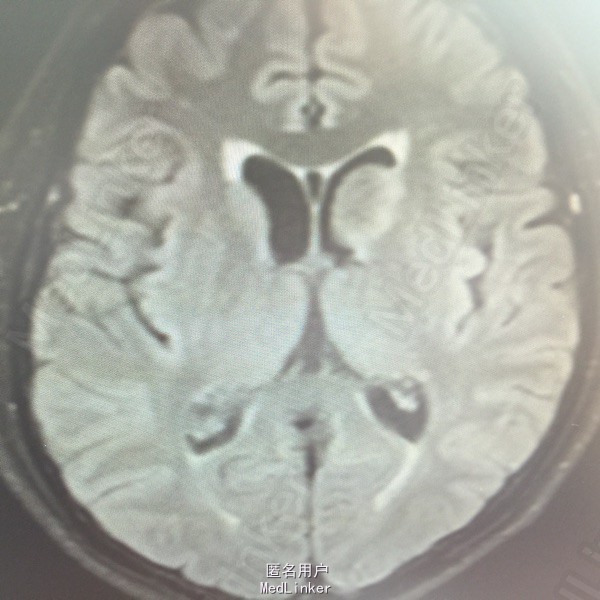

男,54岁,以头痛半个月入院。 现病史:半个月前无诱因头痛,呈胀痛,无呕吐,无意识障碍,病来咳嗽、咳痰,体重减轻约5斤,无发热。 既往史:无特殊。

查体:BP:150/100mmHg,神清语明,两瞳孔等大正圆,直径约3.0mm,光敏,四肢肌力5级,肌张力正常,腱反射艹,左侧共济运动阳性,病理征阳性,脑膜刺激征(-)。 辅查:见下:

肺癌脑转移。 影像解读(影像如何解读是临床工作中非常重要的一环)。 左侧额叶近皮质长Tl长T2信号,局部颅骨缺损,右侧枕叶不规则病灶,TlWl呈中心呈等信号,周围高信号,T2Wl呈高低混杂信号,伴大片水肿,相邻侧脑室后角、胼胝体受压。增强呈不规则环环强化。 已进行局部放疗治疗。